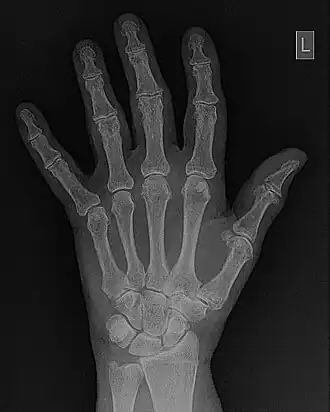

- Contrast enhancement can also be effected through manipulation of the image's statistical histogram and is illustrated in Figure 5.8. A histogram is a plot of the frequency of occurrence of each pixel value in an image - see panel (a) for an example, where this frequency is plotted as a function of pixel value. It can be seen that pixels from the black surroundings of the hand are indicated by the peak at low pixel values. It can also be seen that the pixel values representing bone and tissue attenuation form a broad range of lower frequencies extending to just over half the grey scale. Indeed the pixels of the 'L' marker can be seen to form an isolated blip at a pixel value of 75. Note that the term frequency as used here should not be confused with the term spatial frequency we have been using in our discussion of Fourier techniques.

- Manipulating such histogram data can be used for contrast enhancement by redistributing the pixel values to generate, for instance, a better utilisation of the grey scale. The process of Histogram Equalisation is illustrated in the Figure 5.8, panel (b) along with its histogram - panel (c). It can be seen that the process broadens the frequency distribution so that it now spans the full range of the grey scale. Notice also that the process can generate absent pixel values.:Manipulating such histogram data can be used for contrast enhancement by redistributing the pixel values to generate, for instance, a better utilisation of the grey scale. The process of Histogram Equalisation is illustrated in the Figure 5.8, panel (b) along with its histogram - panel (c). It can be seen that the process broadens the frequency distribution so that it now spans the full range of the grey scale. Notice also that the process can generate absent pixel values.

- Fourier filtering is illustrated in more detail in Figure 5.10. The wrist/hand radiograph of the Figure 5.6 is again used for this illustration. You might remember that its 2D FFT was discussed in an earlier chapter. The filter is shown in panel (c) of the figure in the form of a two-dimensional image. It can be seen that the image data is symmetrical around the centre (i.e.isotropic) where its pixel values are relatively low. Outside this central dark region, a halo of bright pixel values dominates the image as the pixel value trails off slowly towards the periphery. An amplitude profile through this image is shown in panel (d) to further illustrate the effect. The filter can be used to modify the 2D-FFT by multiplying it by the filter values, for instance, to form a filtered 2D-FFT - as shown in panel (e). The Inverse FFT (IFT) of this data is then reveals the filtered image - see panel (f). Given that certain spatial frequencies have been amplified while others have been suppressed with this type of filter, it is called a Bandpass filter.

DICOM-standard images contain what is called a header file which contains information regarding the patient, the examination and the image data - a section of one is shown in the following figure as an example. Note that in this case the image data refers to a hand/wrist image which is stored at a resolution of 2,920x2,920 pixels each of size 0.1 mm. In addition, default window display settings are shown. Furthermore, the form of image compression used can be included, i.e. whether lossless, which preserves the fidelity of image data, or lossy which degrades fidelity in the interest of image transfer speeds, for instance. Numerous other parameters can also be included in a header file.